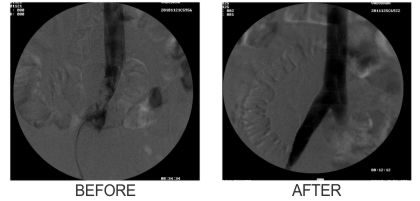

Subclavian Vein Stent